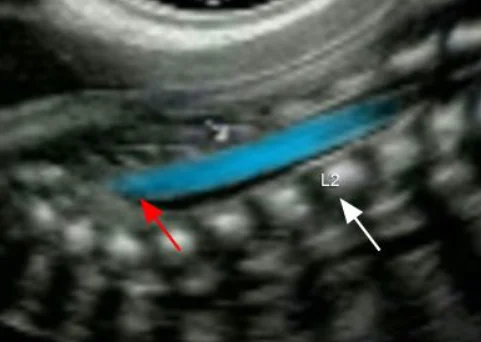

• Giải phẫu cột sống thai nhi

• Chẻ đôi đốt sống (Spina Bifida)